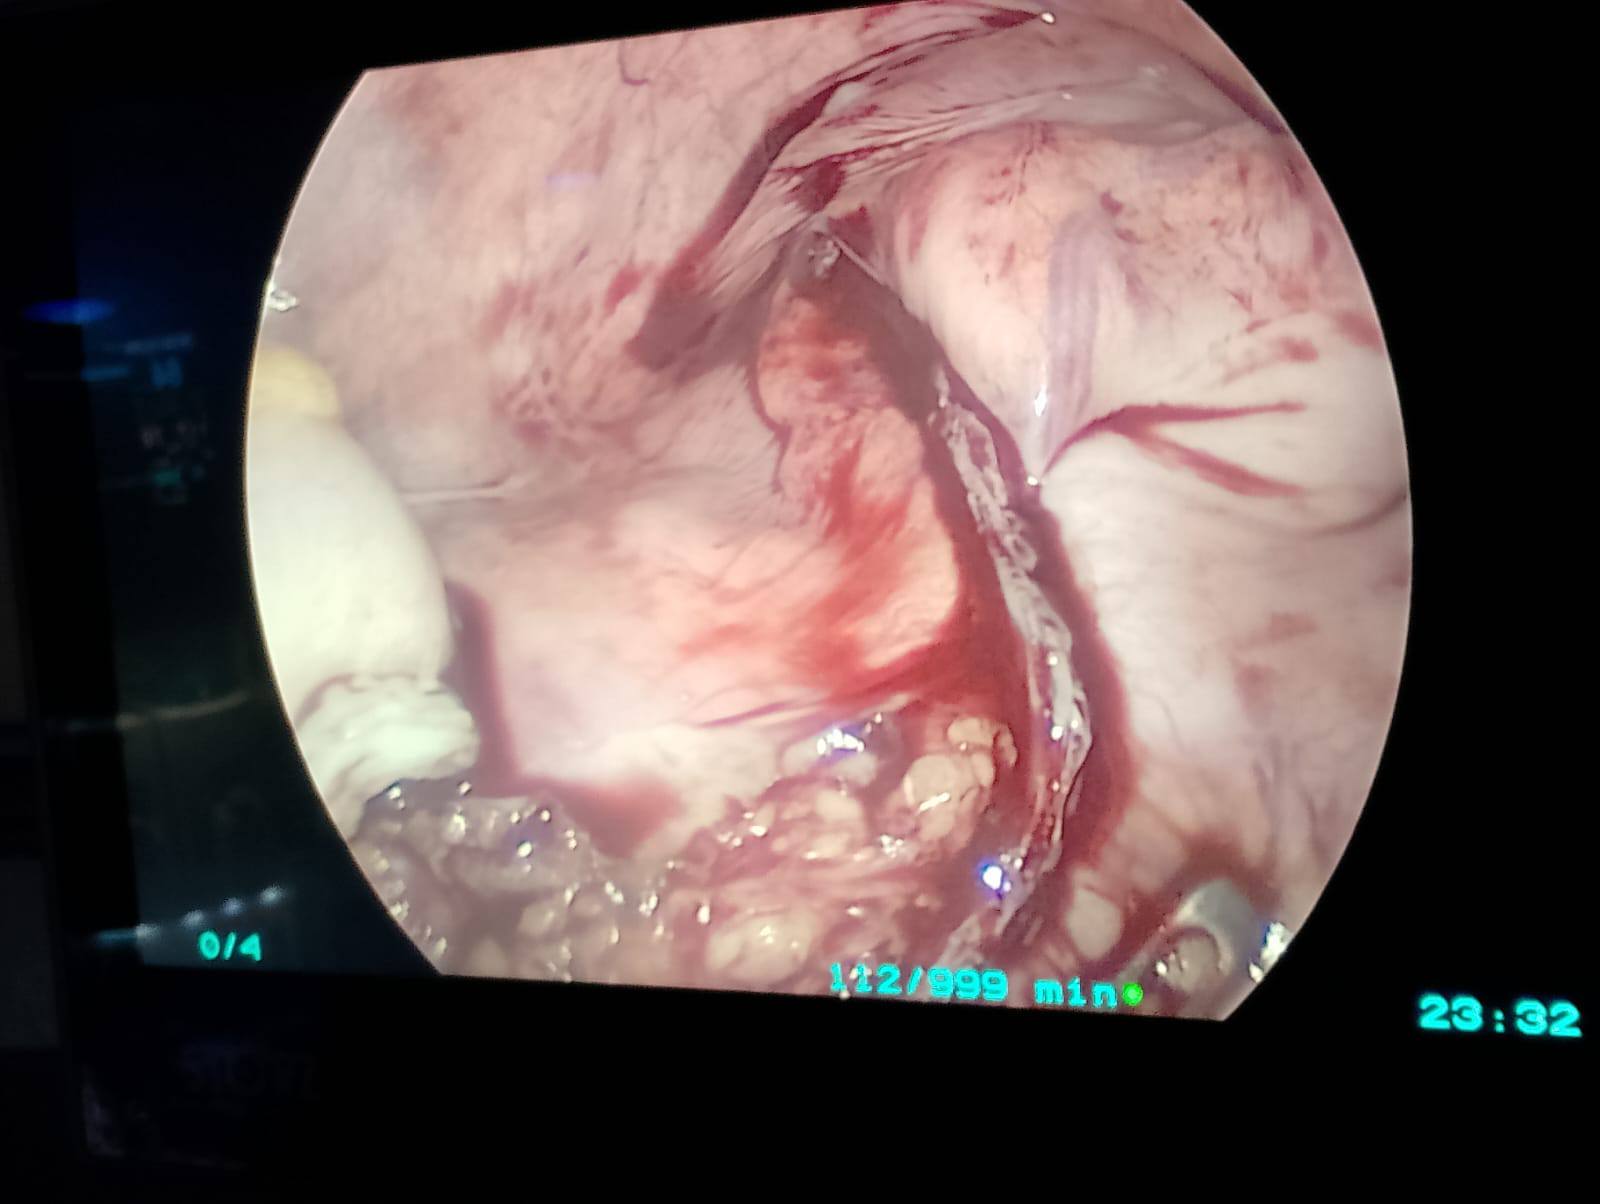

تم اليوم بحمد الله بالمستشفى الجامعى إجراء جراحة متقدمة لاستئصال كلى للقولون بالمنظار الجراحى مع عمل توصيل للأمعاء الدقيقة بالمستقيم لمريض يعاني من انعدام حركية القولون وتم خروج المريض بحالة جيدة بفضل الله.

A case of Laparoscopic total colectomy for a male patient with colonic inertia.